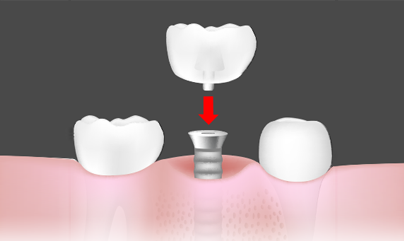

2차 수술 : 보철물 기둥 연결

보철물을 장착할 수 있도록 기둥을 연결하는 2차수술을 한 후, 치아 본을 뜨고 인고치아 보철물을 제작하게 됩니다.

보철물 제작/장찰 및 관리

임플란트가 뼈에 고정된 것을 확인 후 보철물을 제작합니다. 본을 뜨고 맞추는 과정을 마친 후 최종 임플란트 치료를 마칩니다.